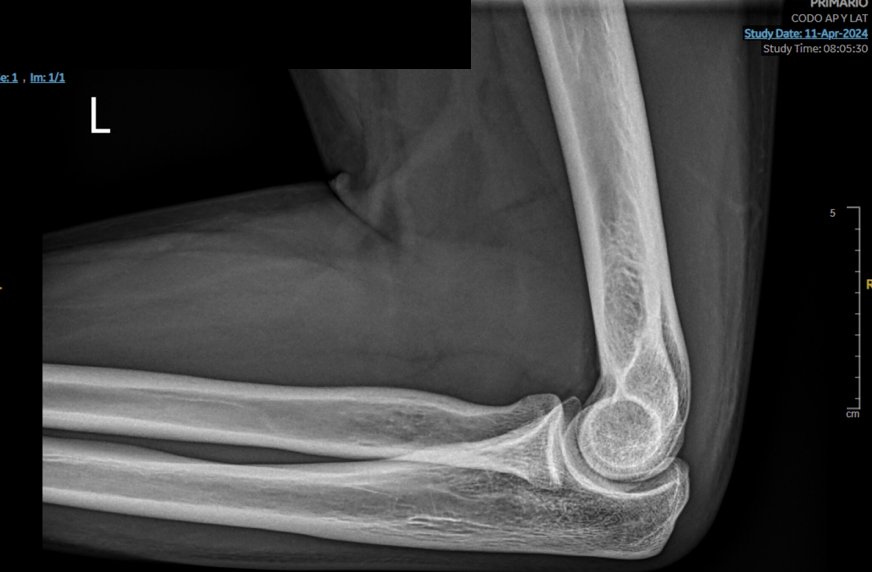

Hombre de 17 años que acude a consulta en agosto de 2024 por dolor y tumefacción a nivel de epicóndilo de codo izquierdo. En abril sufrió una caída contra una palmera y desde ese momento ha consultado hasta en tres ocasiones en Urgencias por dolor. En el informe de urgencias se diagnostica un absceso cutáneo de 1 cm de diámetro y se solicita una radiografía de codo (sin alteraciones). Se alta con antibioterapia. En consulta persiste la sintomatología. Se revisa la radiografía y se repite la exploracion física: tumefacción de 1,5 cm de diámetro en epicóndilo izquierdo. Se decide realizar una ecografía músculoesquelética con identificación de un cuerpo extraño tras lo que se procede a su extracción que resulta ser una púa de 2,6 cm.

Al inicio se sospechaba una reacción cutánea a cuerpo extraño no evidenciado en radiografía que se confirmó mediante ecografía.

Diagnóstico final: reacción cutánea a cuerpo extraño (púa de palmera).